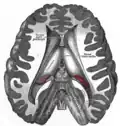

Imágenes adicionales

El cuerpo pineal está etiquetado en estas imágenes.

Aspecto mesal de un cerebro seccionado en el plano sagital mediano. -

Disección que muestra los ventrículos del cerebro. -

Vista anterolateral de las regiones medias y traseras del cerebro. -

Sección sagital mediana del cerebro. -

Glándula pineal.

-

Tronco encefálico. Vista posterior.